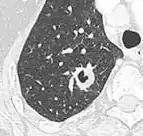

- A bulla has a wall thickness of less than 1 mm.[2] By radiology definition, is has a total size of greater than 1 cm.[3] By pathology definition, it originates in the lung parenchyma (rather than in the pleurae).[4]

| CT scan of the lung showing bullae in the lower lung lobes of a subject with type alpha-1-antitrypsin deficiency. There is also increased lung density in areas with compression of lung tissue by the bullae. | |